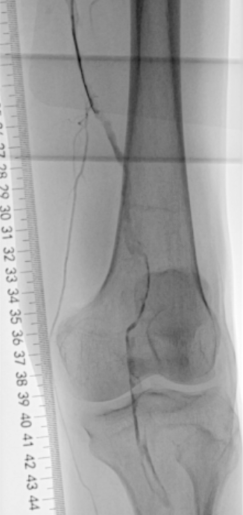

术前下肢动脉CTA提示:左下肢股、腘动脉长段闭塞,膝下动脉主干未见显影,可见少量侧支血流。

血管外科姜坤主任团队仔细分析患者病情,该患者在动脉硬化闭塞基础上继发血栓形成,且血栓负荷量大,身体状况差,行麻醉及开放手术取栓的风险大,遂制定了微创腔内的手术方案,采用动脉机械血栓清除+血管成形术。

术中选用Rotarex导管行血栓清除,对管腔内残留的血栓放置溶栓导管,最后采用球囊扩张狭窄病变,管腔获得满意。